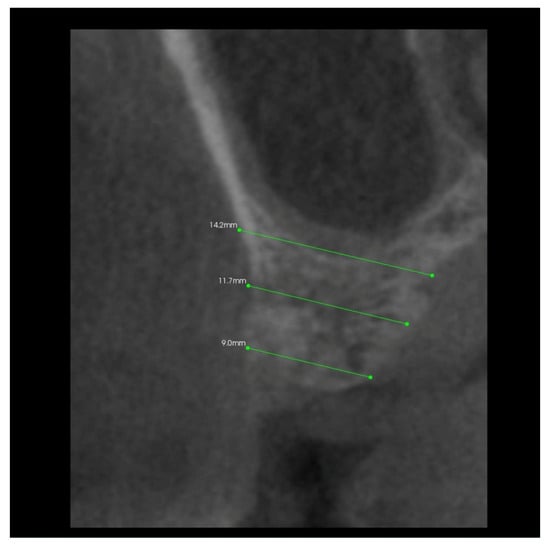

3.2. The Results of Mean Values of the Alveolar Process Width and Height Measurements Performed after Tooth Extraction within the Space of 6 Months for Two Different Alveoli in the Same Patient

3.4. The Results of Mean Measurements of Height and Width of the Alveolar Processes of Two Extraction Sites (with and without PRF) in the Same Patient after 6 Months from Tooth Extraction Based on the Analysis of Volumetric Tomography